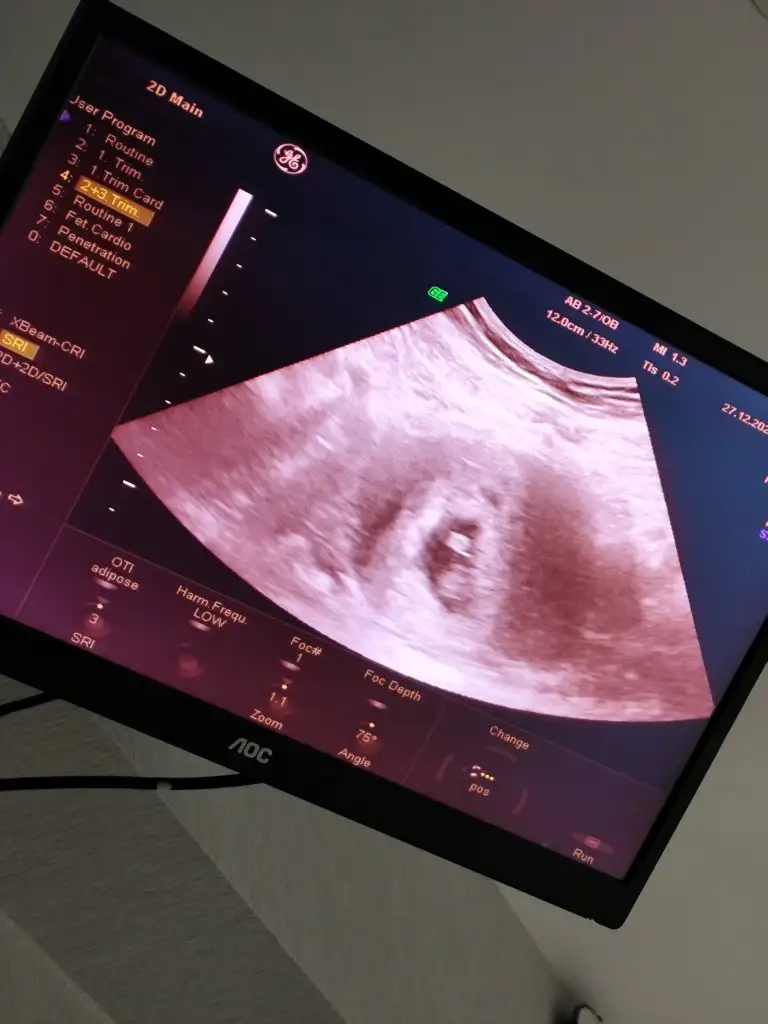

Gittim doktora kalp atışını da duydum her şey yolunda çok şükürCanım nasılsın nasıl çıktı sonuçların inşallah güzel haberler alırsın

Oh bee günün en güzel haberiGittim doktora kalp atışını da duydum her şey yolunda çok şükür8+5 günlük oldu